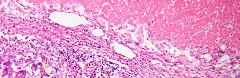

prep20tumor = Karzinome und Tumore (Geschwulste): Leber-Karzinom, primäres und sekundäres, Lungen-Karzinom, Magen-Karzinom, Schilddrüsen-Karzinom, Colon-Karzinom (Dickdarm), Rektum-Karzinom (muzinöses), Rektum-Adenokarzinom, Haut-Krebs (squamös / Schuppenhaut), Melanosarkom (Melanom), Brust-Krebs, Cervix-Karzinom (Gebärmutterhalskrebs), Hoden-Karzinom, Preaputium (Vorhaut) Krebs, Leukämie (Blutausstrich), Milz bei chronischer myeloischen Leukämie, Ovar (papilläres Zystadenom - gutartig), Uterus-Myom (Gebärmutter - gutartig), Uterus-Fibroadenom (Gebärmutter - gutartig), Brust-Fibroadenom (gutartig). (Bild: ganz unten)

prep20tumor = Karzinome und Tumore (Geschwulste): Leber-Karzinom, primäres und sekundäres, Lungen-Karzinom, Magen-Karzinom, Schilddrüsen-Karzinom, Colon-Karzinom (Dickdarm), Rektum-Karzinom (muzinöses), Rektum-Adenokarzinom, Haut-Krebs (squamös / Schuppenhaut), Melanosarkom (Melanom), Brust-Krebs, Cervix-Karzinom (Gebärmutterhalskrebs), Hoden-Karzinom, Preaputium (Vorhaut) Krebs, Leukämie (Blutausstrich), Milz bei chronischer myeloischen Leukämie, Ovar (papilläres Zystadenom - gutartig), Uterus-Myom (Gebärmutter - gutartig), Uterus-Fibroadenom (Gebärmutter - gutartig), Brust-Fibroadenom (gutartig). (Bild: ganz unten)